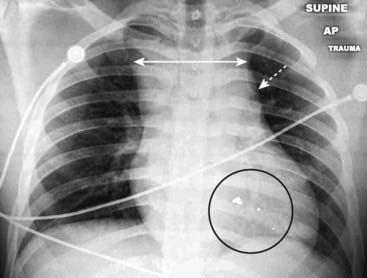

image

Figure 17-5 Mediastinal hematoma.

There is “widening of the mediastinum” (double white arrow), an inexact finding on an AP supine, portable chest radiograph. More importantly, the shadow of the aortic knob is obscured by something of soft tissue density (dotted white arrow). Because the patient had been shot (bullet fragments in the black circle), these findings led to a request for a CT scan of the chest which demonstrated a large mediastinal hematoma.